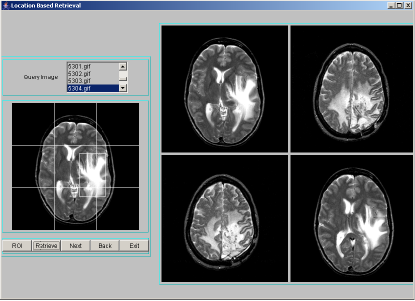

Location Based Indexing and Retrieval is performed by finding spatial location of a segmented region. The importance of location of objects is to identify the area of involvement of tumor like sensory or motor. The brain has unique areas for speech, hearing, visual, temperature regulation etc.. If the tumor which may not be centrally located, occurs at any particular area/location, then the corresponding organ gets affected. Hence location is an important feature to be indexed. To compute the location of a region, we divide the image space into 3x3 grid cells and number them 0-8 as shown in Figure 2. The region is likely to overlap number of cells in the image space. The index assigned is the cell number that is maximally covered by the region. A program segment to find location of a region is given in Table 5. We have considered an image size of 256x256 pixels in our work. The position of a region forms the location index. For each image in the database, segmentation procedure is applied to identify region-of-interest and describe segmented region by texture features: entropy, energy and contrast. Each location index stores region texture feature data along with the image object. For a query image, after finding the region-of-interest, the above mentioned texture features have to be computed and the location index is derived. Only those images that are stored at the location index matching those of the query index, are extracted as resultant target images for a given query image. These resultant images are sorted using Euclidean distance measure in the decreasing order of similarity against the query image and displayed four images at a time using JAVA-AWT based GUI. A few representative snapshots of location-based indexing and retrieval are shown in Figure 2.

|

|